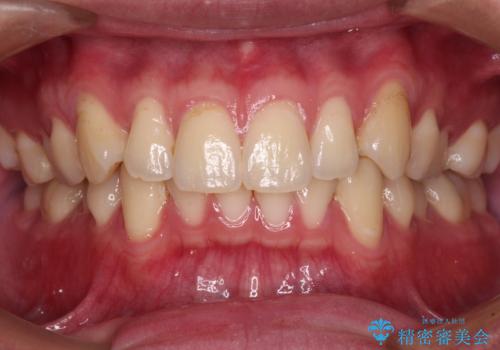

デコボコの歯とむし歯 インビザライン矯正治療とむし歯治療